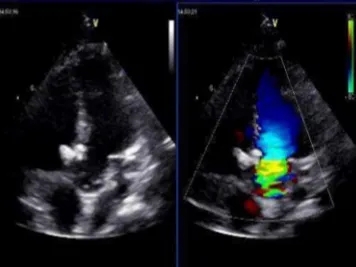

术后1个月随访:

超声提示:

先天性心脏病,室间隔缺损封堵术后:

可降解封堵器位置固定,形态正常

左室收缩功能正常;

彩色血流提示:室水平未见分流;三尖瓣反流(少量)

两次随访中,MemoSorb全降解封堵器形态稳定、无位移、无残余分流、无主动脉瓣反流,三尖瓣反流与术前无明显差异。